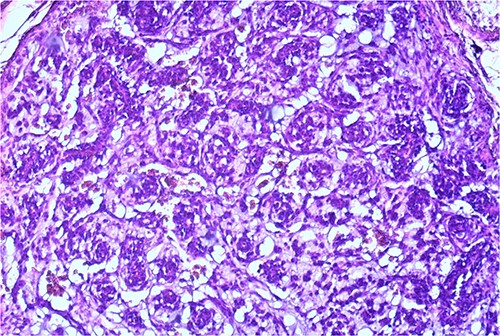

The macroscopic pathology report revealed the total dimension of the removed tissue to be 10.5 × 8.5 × 10.5 cm. However, the tumor itself had dimensions of 8 × 7.5 × 7 cm, surrounded by a pseudo capsule. The tumor was described to be multicystic, formed by loculi filled with hemorrhagic and partially with yellowish gelatinous myxoid content. In its periphery, yellowish tumor tissue was present (Fig. 3). Microscopic findings described a tumor made of myxoid stromal nodules and small capillaries concentrically surrounded by monomorphic round cells with mild nuclear pleomorphism. Large pseudo-angiomatous spaces filled with blood were seen in some of the nodules. Part of the nodules was hypocellular, made mostly by myxoid stroma and stellate cells. A thick fibrous pseudo capsule with numerous multifocal deposits of hemosiderin deposits was present peripherally. Tumor tissue infiltrates the abdominal wall muscles (Figs 4 and 5).

Small capillaries lined by relatively monomorphous round cells, with mild pleomorphism and sparse mitotic activity, surrounded by myxoid stroma (HeEo, ×100).